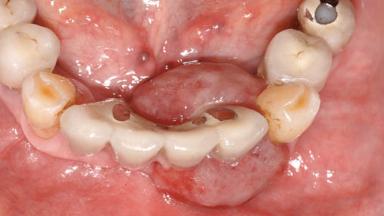

| # of Teeth | 10 |

| # of Implants | 5 |

| Prosthesis Type | FDP |